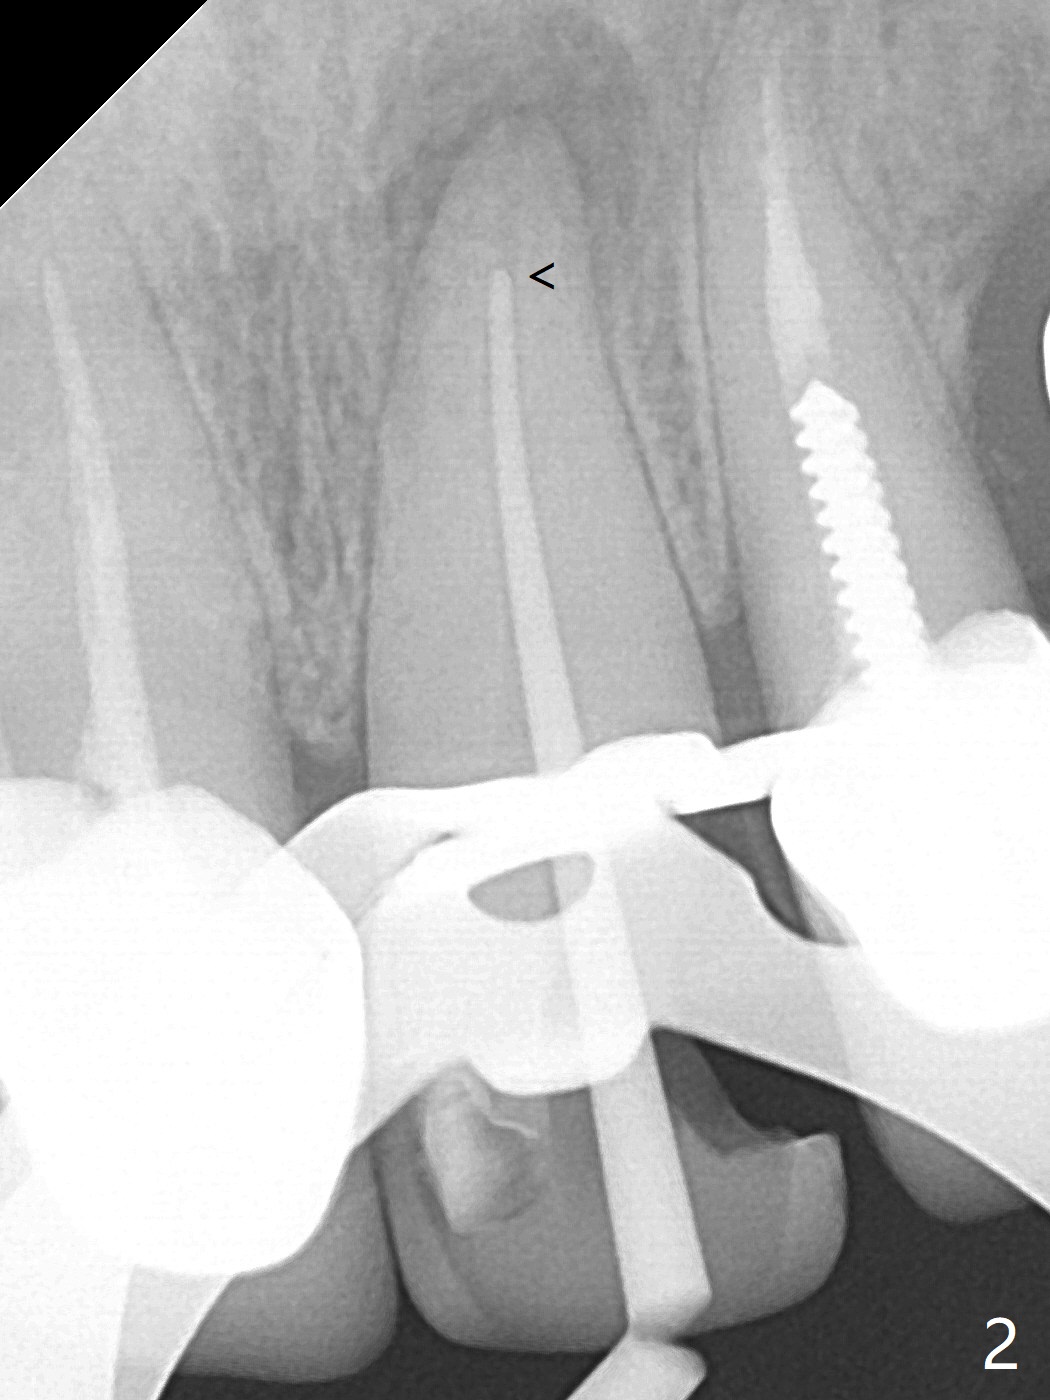

62岁女因牙痛(图一)做根管治疗(图二,三)。一年10个月后因11,13,30,31 植牙,拍摄CT,根尖阴影明显缩小(图四,五)。颊侧骨板薄而短(图四:>),牙槽骨也狭窄,如果需要植牙,比较困难。